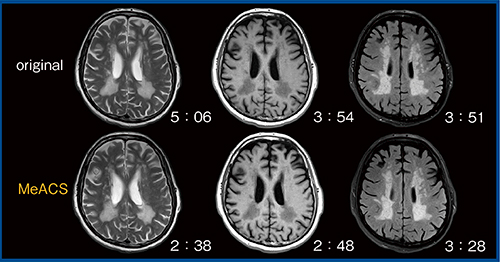

また,一般的なcompressed sensingは,T1強調やFLAIRなど,低組織コントラスト画像に適用すると画質の変化が大きい。一方,MeACSではコントラストを維持したまま高速化が図れている(図5)。

図5 低組織コントラスト画像におけるMeACSの有用性(W.I.P.)